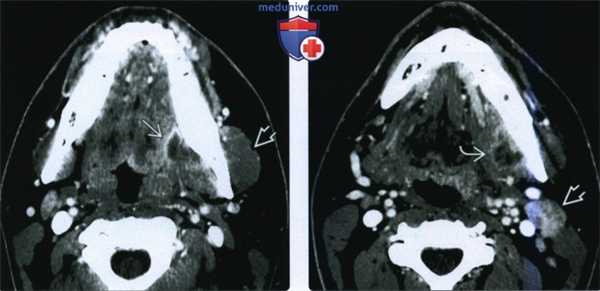

(Слева) На аксиальной КТ с КУ определяется большой многокамерный абсцесс внутреннего ЖП с вовлечением крыловидных мышц. Обратите внимание на утолщение и отек жевательной мышцы в наружном жевательном пространстве. У этого пациента 21 года девять месяцев назад был удален моляр слева, после чего появилась оталгия в сочетании с тризмом, неверно расцененные как проявления синдрома ВНЧС.

(Справа) На аксиальной КТ с КУ у этого же пациента определяется дальнейшее распространение абсцесса внутреннего ЖП в и отек жевательной мышцы.

(Слева) При КТ с КУ в аксиальной проекции определяется гигантский многокамерный абсцесс медиальных отделов жевательного пространства, распространяющийся на крыловидные мышцы. Обратите внимание на отек и припухлость жевательной мышцы в латеральном жевательном пространстве. Пациентка - девушка 21 года, которой девять месяцев назад был удален левый нижний моляр. Все это время она предъявляла жалобы на тризм и боль в ухе, которые врачи ошибочно принимали за заболевание височно-нижнечелюстного сустава.

(Справа) При КТ с КУ в аксиальной проекции у этой же пациентки видно, что абсцесс распространяется в нижележащие ткани. Также имеется отек жевательной мышцы.